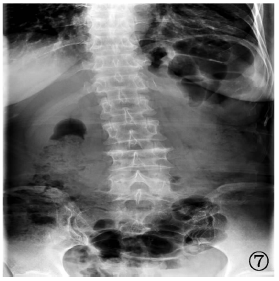

| 图7 病例5,男性,62岁,2019年1月14日,患者于陕西省结核病防治院摄腰椎正位片,显示腰4~5椎体骨质破坏,椎间隙变窄,椎旁软组织增厚 |